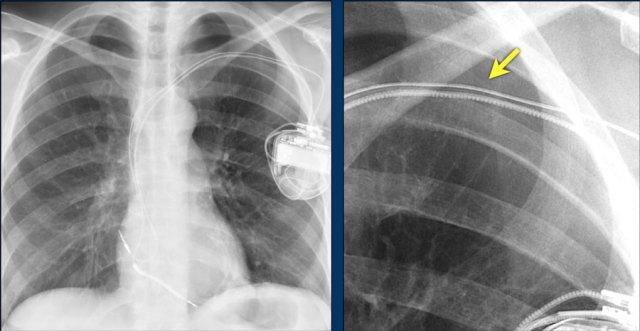

Hình ảnh được chụp ngay sau khi đặt ICD.

Có hình ảnh tràn khí màng phổi nhỏ (mũi tên).

Đây là biến chứng thường gặp nhất.